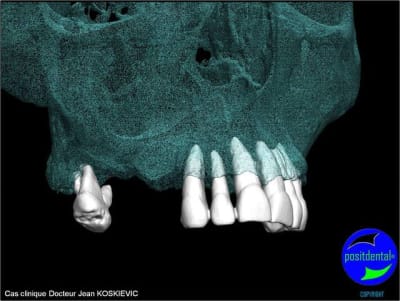

rendu 3D maxillaire sup, pano et photo

3D maxillaire inférieur et photo